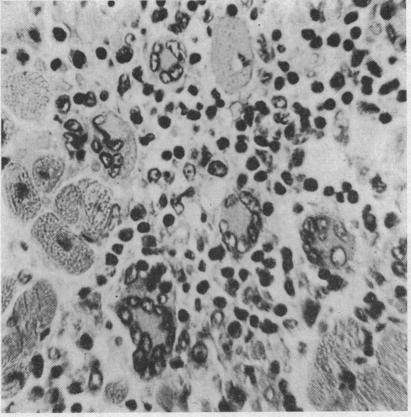

FIEDLER'S MYOCARDITIS.

Br Heart J. 1965 May;27(3):458-61. doi: 10.1136/hrt.27.3.458.

Acute idiopathic interstitial myocarditis: case report with special reference to morphological characteristics of giant cells.急性特发性间质性心肌炎:病例报告并特别提及巨细胞的形态学特征